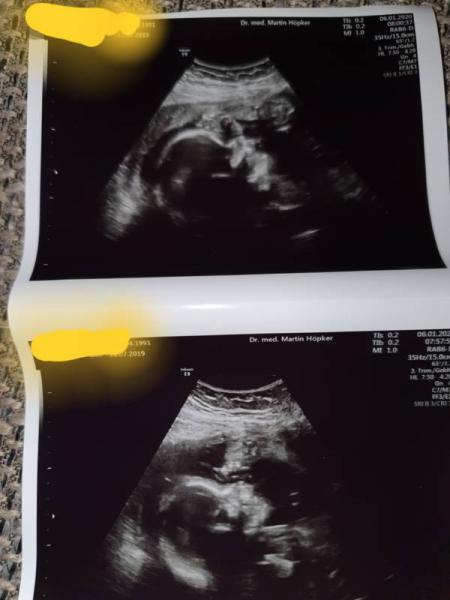

Heute wieder Untersuchung gehabt und es ist alles prima. Der kleine ist soweit zeitgerecht entwickelt Haben versucht ein 3d Foto zu bekommen aber er hatte die ganzen Zeit die Hände vorm Gesicht Er hat gewunken und uns die Zunge rausgestreckt und er hat saugbewegung gemacht. Es war so toll ihn dabei zu beobachten. Er ist jetzt 28 cm und wiegt 680 gramm Am 13 hab ich den zuckertest und hab jetzt schon grauen davor, bei der großen mit Mühe und Not drin behalten

Bild zu Zurück vom Doc - Forum für April - Mamis